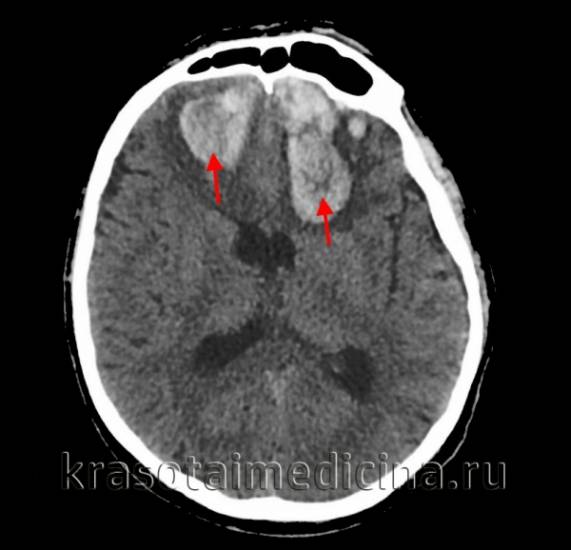

image

КТ головного мозга. Внутримозговые (интрапаренхиматозные) травматические гематомы с обеих сторон